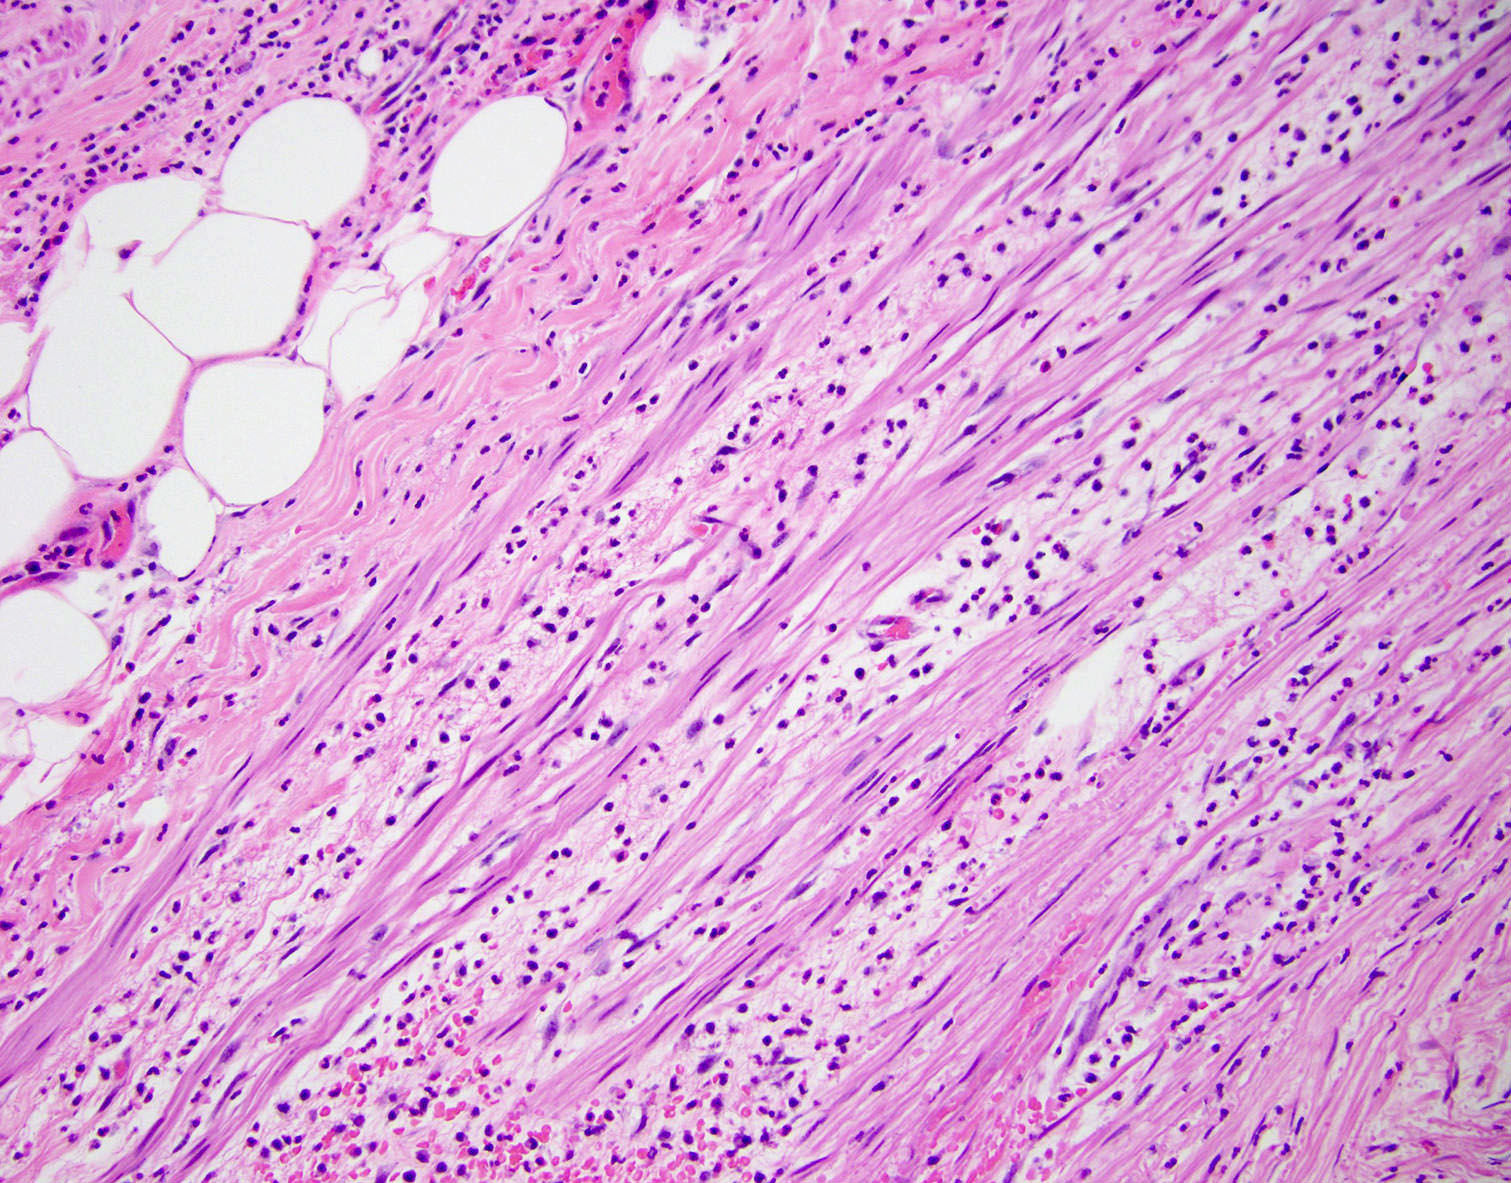

Microscopic (histologic) description

- Variable acute inflammation with predominance of neutrophils; involves some or all layers of the appendiceal wall

- Process may be divided into acute focal, acute suppurative, gangrenous and perforative

- Early lesions display mucosal erosions and scattered crypt abscesses

- Later, the inflammation extends into the lamina propria and collections of neutrophils are also seen in the lumen

- Mural necrosis in gangrenous appendicitis

Microscopic (histologic) images

A 40 year old caucasian man presented into the emergency room with right lower quadrant pain associated with vomiting, abdominal tenderness, fever and moderate leukocytosis. Acute appendicitis was suspected and he underwent an appendectomy. His appendix was sent to pathology for histological evaluation. The H&E images are shown above. Which of the following is the most likely diagnosis?

A 35 year old woman presented with localized right lower quadrant abdominal pain for 1 day. She also presented with nausea, vomiting, menorrhagia and dizziness. She reported that she was actively menstruating and that these symptoms typically occurred monthly with menstruation but had been particularly severe in that month. CT scan showed thick walled appendix consistent with acute appendicitis. She underwent an appendectomy. The H&E images are shown above. Which of the following is the most likely diagnosis?